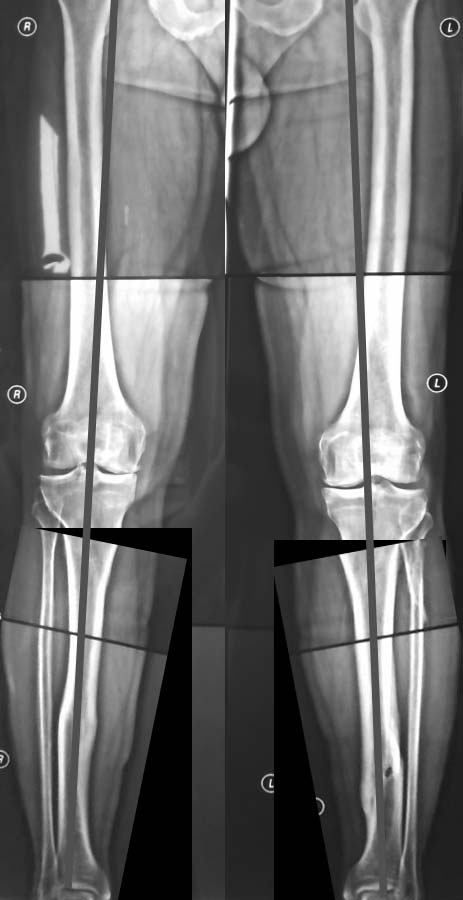

Уважаемый Тарас Рокита,

Обе большеберцовые кости имеют 2 вершины деформации, т.е. речь идет о двухуровневых корригирующих остеотомиях. И только после этого ставить вопрос об одномыщелковом протезировании. При тотальном протезировании, возможно, можно будет обойтись только диафизарными остеомиями

(дистальная CORA). К сожалению, точнее сказать не могу - для расчетов Рг низкого качества.